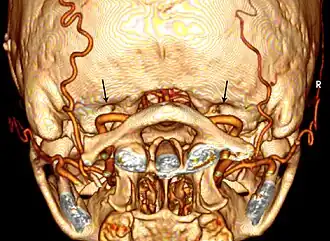

Bilateral condylar canals (arrows) above the vertebral arteries.

Bilateral condylar canals (arrows) above the vertebral arteries. -